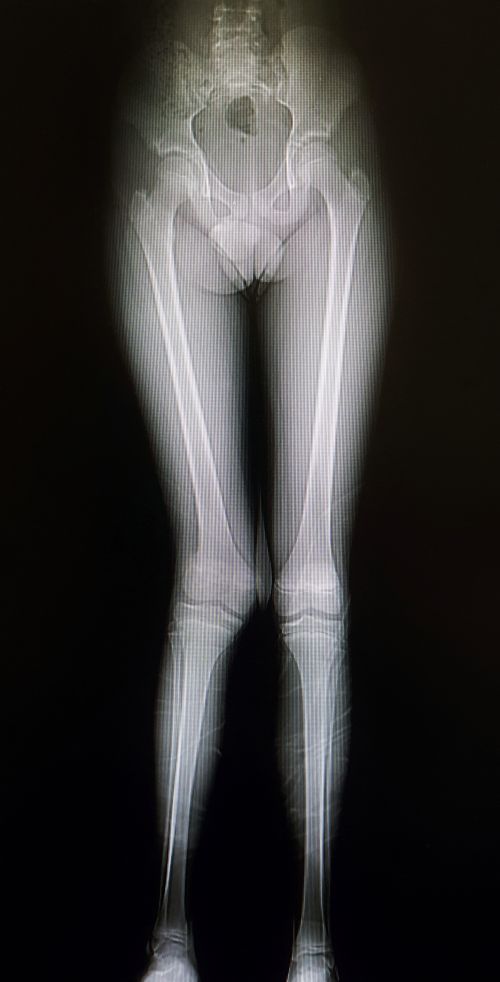

3. Lábhosszkülönbség

Néhány korábbi tanulmány összefüggést mutatott a lábhosszkülönbség és a derékfájdalom között (22,26). Két kutatás szerint a lábhosszkülönbség azért vezet derékfájdalomhoz, mert oldalirányú medence billenést és ágyéki gerincferdülést okoz (27,28). Schaffer (29) ugyanakkor egy másik, potenciális utat vázolt fel: a lábhosszkülönbség anterior rotációt okoz a rövidebb láb oldalán és posterior rotációt a hosszabb lábén. A csípőcsontok rotációja mintegy továbbgyűrűzve keresztcsont billenéshez (tilt) vezet, ami a lumbosacralis (ágyéki-keresztcsonti) régiót is érinti. Hoikka és mtsai (30) ugyanakkor elvetik a fenti hipotéziseket. Kimutatták, hogy a lábhosszkülönbség és a keresztcsont billenése között igen korlátozott a kapcsolat, a lábhosszkülönbség és a lumbális scoliosis közti összefüggés pedig még ennél is kisebb mértékű. Számos már kutatás vezetett Hoikkáékéhoz hasonló eredményre, azaz kérdőjelezi meg az összefüggést a lábhosszkülönbség és a derékfájdalom között (31-35)